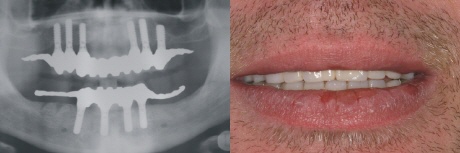

Endergebniss - Bissfest

Ein zufriedener Patient mit einem erheblichen Gewinn an Lebensqualität ist sicher versorgt und bissfest hoffentlich sein Leben lang.